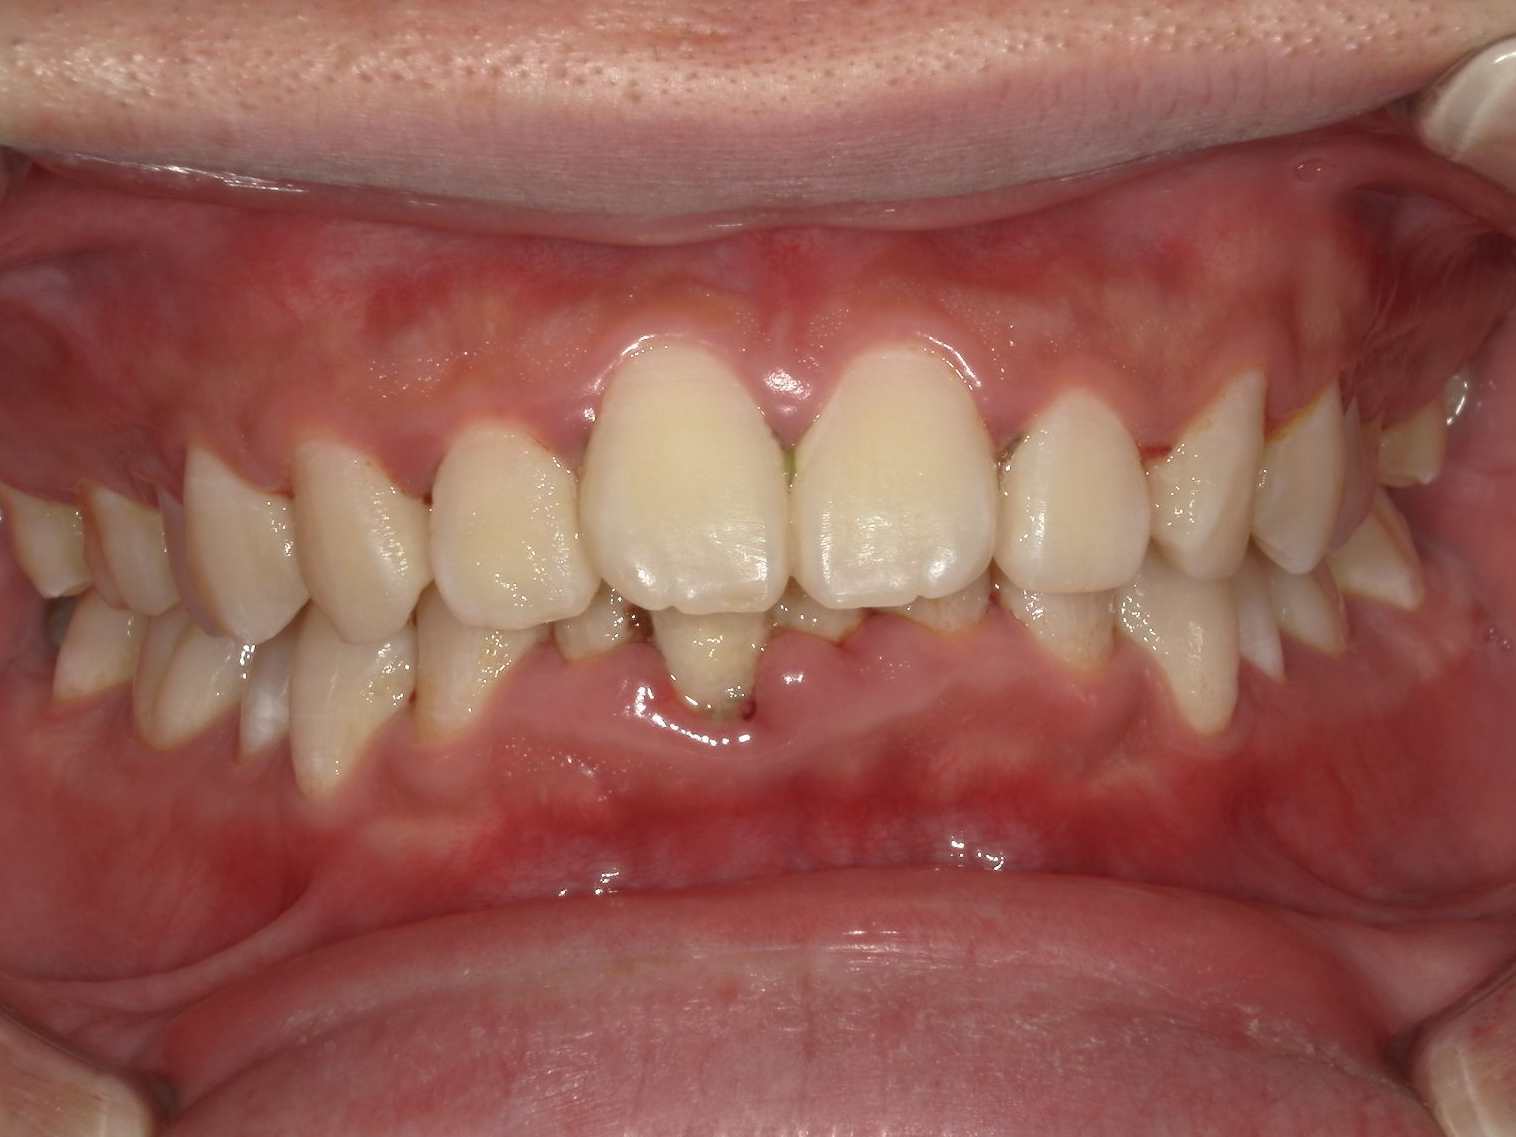

治療前